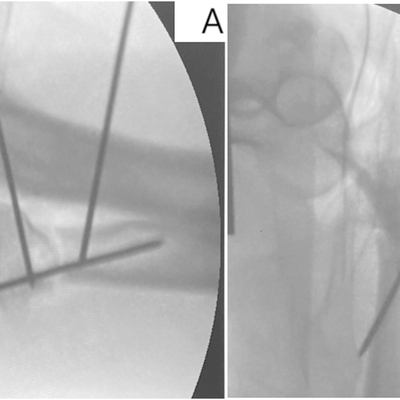

Click on an image below to view more info.